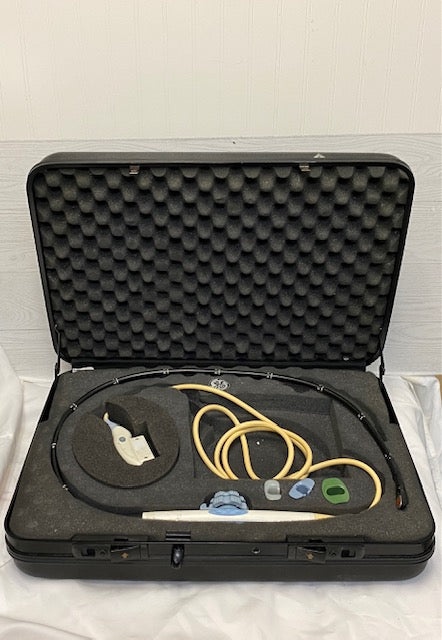

DIAGNOSTIC ULTRASOUND MACHINES FOR SALE